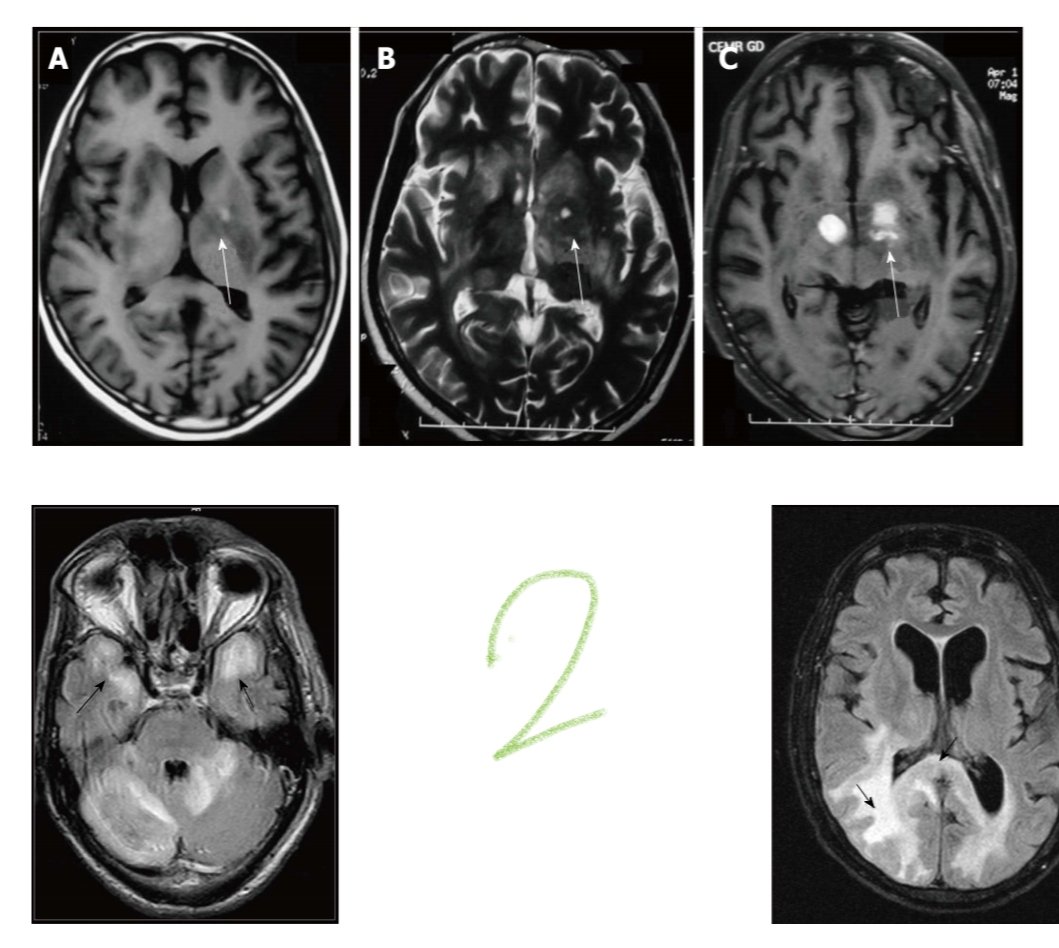

Basal ganglia SOL etiologies:

8:Toxoplasmosis, Gd enhancement, no DWI restriction, decreased perfusion, MRS lipid peaks.

9:Primary CNS lymphoma, Gd enhancement, marked DWI restriction, increased perfusion, MRS choline peak.

10: Cryptococcosis, no Gd enhancement, DWI restriction. ImageImageImageImage